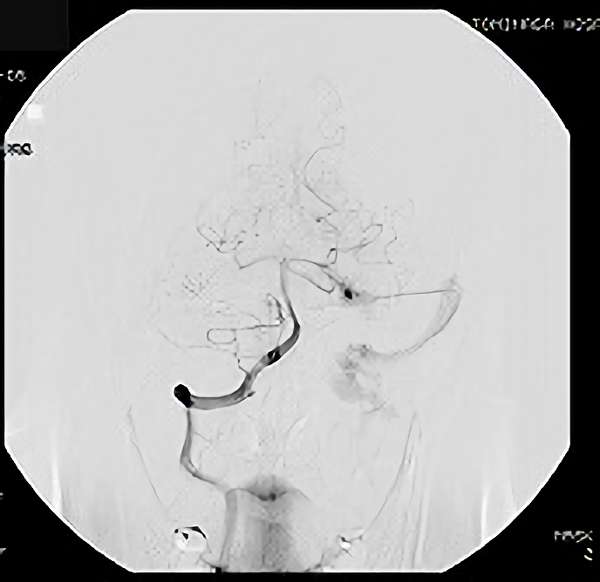

'19年5月

30代

富永/久貝

右中小脳脚 出血再発

SM 3(S1,E1,V1)

米国の病院

No.359 モニタリング

No.359 手術前

No.359 手術中

No.359 手術後

出血既往があり。2回の手術前血管内手術の後に、

Lateral transpeduncular approachにより再々出血予防を目的に

摘出手術を行う。完全摘出であることを確認した。

手術による合併症や後遺症なしで退院した。経過良好。